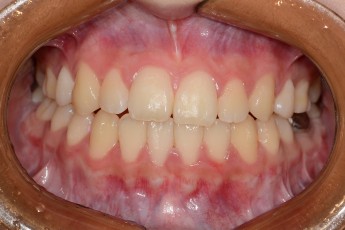

Before & After

Before

After